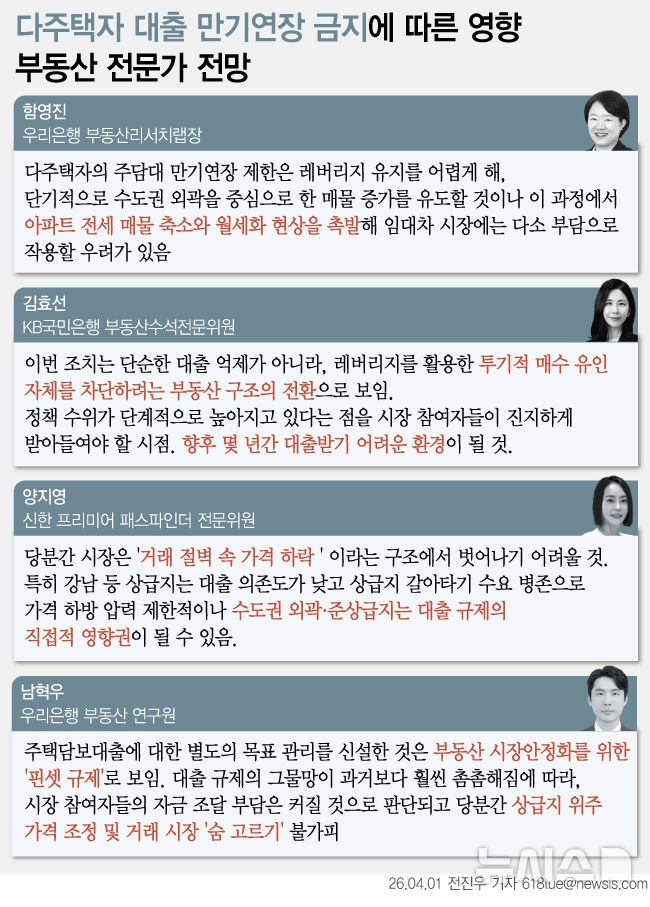

![[서울=뉴시스] 무증상 일시적 면역관련 폐렴 사례. (사진= 서울대병원 제공)](https://img1.newsis.com/2025/11/25/NISI20251125_0002001705_web.jpg?rnd=20251125102049)

[서울=뉴시스] 무증상 일시적 면역관련 폐렴 사례. (사진= 서울대병원 제공)

이에 연구팀은 치료 중 나타난 이상반응 양상에 따라 환자를 ▲이상반응이 전혀 없는 '무이상반응군' ▲임상 증상이나 혈액검사 이상을 동반한 '증상성 이상반응군'(증상군) ▲증상은 없지만 CT에서 폐 주변부 미세 염증성 음영, 일시적 대장벽 비후, 장간막 염증, 반응성 림프절 종대 등 면역반응으로 해석되는 변화만 나타난 '무증상 영상 이상반응군(무증상 영상군)'으로 분류했다. 전체 198명 중 무증상 영상군은 12명, 증상군은 56명, 무이상반응군은 130명이었다.